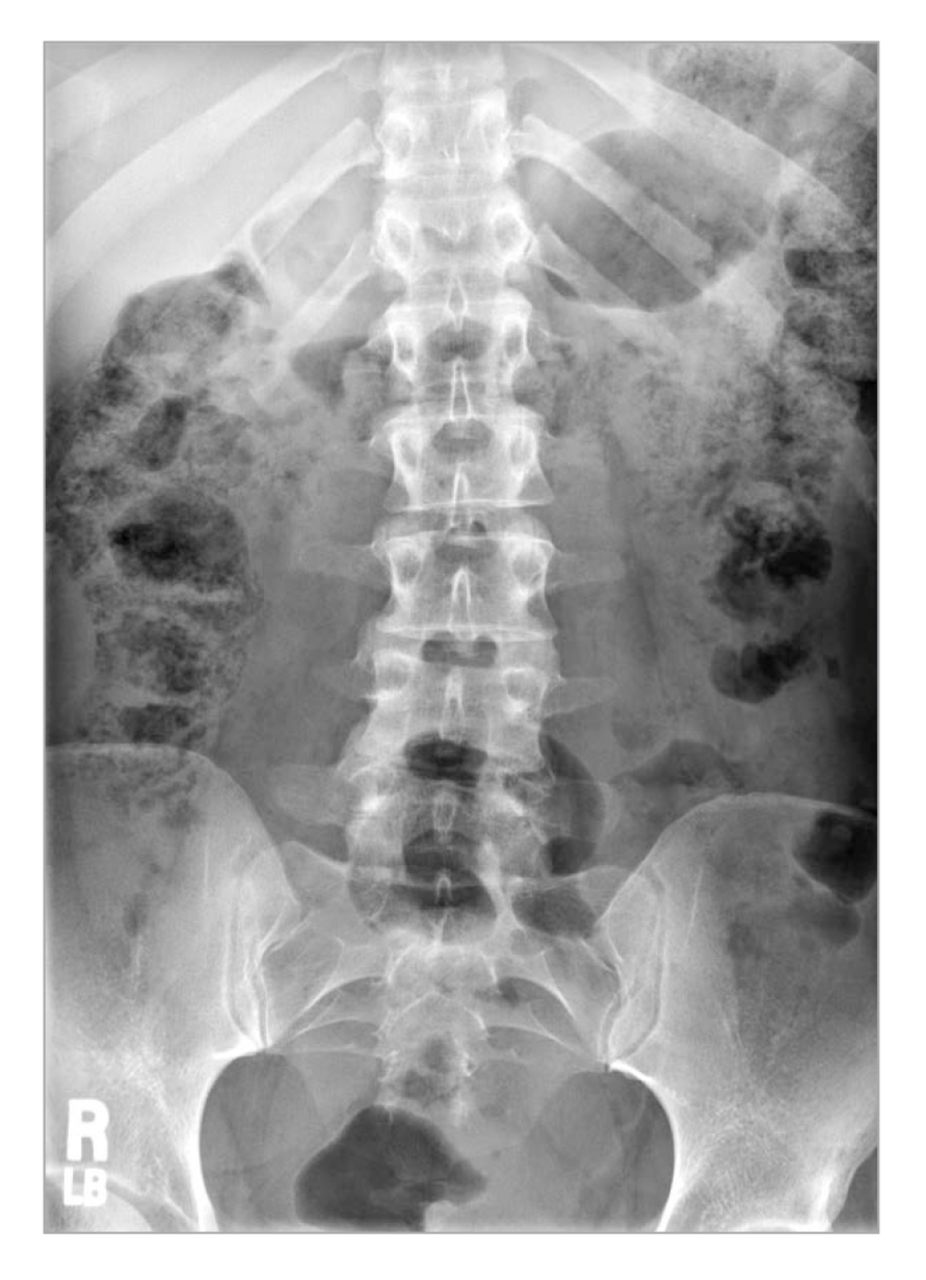

A plain radiograph (Figure 1) of the lumbosacral spine revealed a mild left convex scoliosis. All lumbar disk spaces were found to be normal, and no degenerative changes were present. No acute findings were noted. A radiograph of the patient's hips did not reveal any abnormalities.

Lumbosacral plain radiograph exhibiting mild left convex scoliosis.